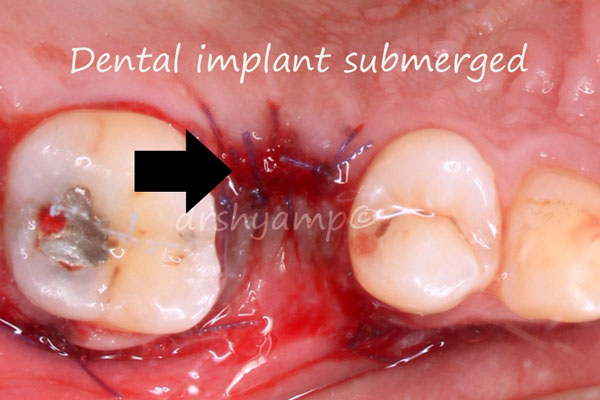

immediate dental implant

immediate dental implant

immediate dental implant

immediate dental implant

immediate dental implant

immediate dental implant

immediate dental implant

immediate dental implant

immediate dental implant